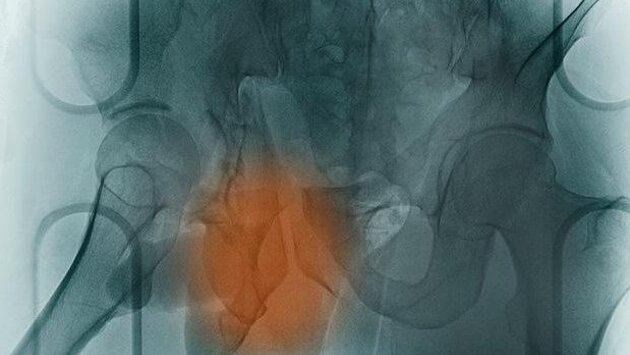

Британские ученые испытывают новую методику лечения остеопороза с помощью стволовых клеток, которые становятся новыми костями. Для этого используется специфическая вибрация. До сегодняшнего дня единственным выбором для пациентов с остеопорозом, столкнувшихся со сложными переломами, является очень болезненная хирургическая операция. Во время нее врачи удаляют кости из здоровой части тела и трансплантируют их на поврежденную зону. Однако британские исследователи установили, что стволовые клетки могут превращаться в клетки костей (остеобласты) при помощи вибраций низкой интенсивности. Стволовые клетки уже давно считаются будущим медицины, поскольку они обладают способностью трансформироваться в любые клетки организма в зависимости от потребностей. Исследователи из Университета Восточной Шотландии и Университета Глазго полагают, что вибрации при частоте в 1000Hz повторяют условия, с которыми сталкивается натуральная кость в организме. А это побуждает стволовые клетки превращаться в кости в течение 28 дней, чтобы потом быть имплантированными. Авторы методики надеются, что та же самая частота вибрации может быть использована для стимуляции заживления внутри тела даже без трансплантаций. Они подчеркивают, что подобного рода вибрации организм человека испытывает постоянно от различных механических стимуляций вроде ходьбы пешком или сердцебиений. Данная методика использует механоэлектрические свойства костей, конвертирующих механический стресс в электричество, что и происходит при частоте в 1000Hz. Доказано, что кости сохраняют свое здоровье только при активных нагрузках, и поэтому космонавты достаточно быстро теряют костную массу в условиях гравитации. Именно поэтому для трансформирования стволовых клеток в кости используется техника вибрации. (ЧИТАТЬ ДАЛЕЕ)